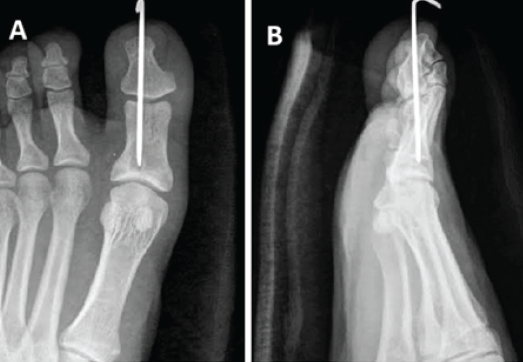

The extensor expansion was meticulously repaired to restore tendon continuity. Layered closure of the wound was performed, followed by the application of a sterile dressing. The hallux was immobilized postoperatively to protect fixation and facilitate healing, as shown in post-operative image (Fig. 5a and b). The mean K-wire removal time was 6–8 weeks. At a mean follow-up of 6 months (Fig. 6a and b), three patients had a full, pain-free range of motion, while two developed mild stiffness but were asymptomatic in daily activities. None had residual pain, instability, or recurrence of dislocation.

Figure 5: These are the post-operative images in anteroposterior and lateral view showing temporary fixation of the interphalangeal joint of the great toe with a 2.5 mm K-wire due to instability (a and b).